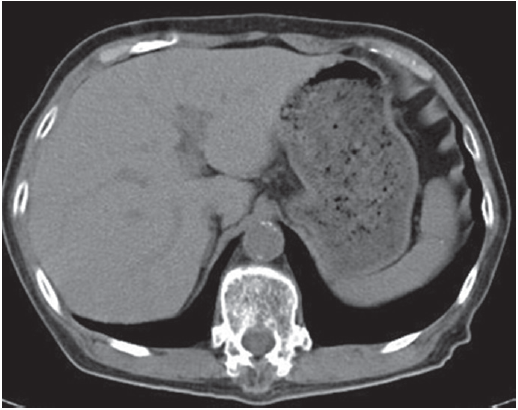

Abdominal plain computed tomography (CT) revealed an increased liver density (Fig. 1). These disorders were determined to be attributable to an overdose of amiodarone, and the drug was discontinued. Thyroid hormone replacement relieved her dementia; the dosage of thyroid hormone preparations was decreased over time and eventually discontinued. Moreover, the liver dysfunction gradually resolved. An abdominal plain CT scan performed 1 year later revealed a decrease in the high liver density (Fig. 2). During this period, no recurrence of paroxysmal atrial fibrillation was detected.

Figure 1.

Abdominal plain computed tomography scan. Markedly increased liver density is observed.